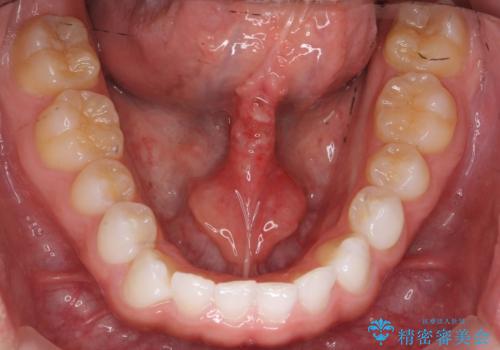

- 舌小帯の切除を希望して来院。

口を大きく開けた時に、上顎に舌がつかない状態でした。

切除後、しっかり上にもつくようになり、前にも大きく出せるようになりました。